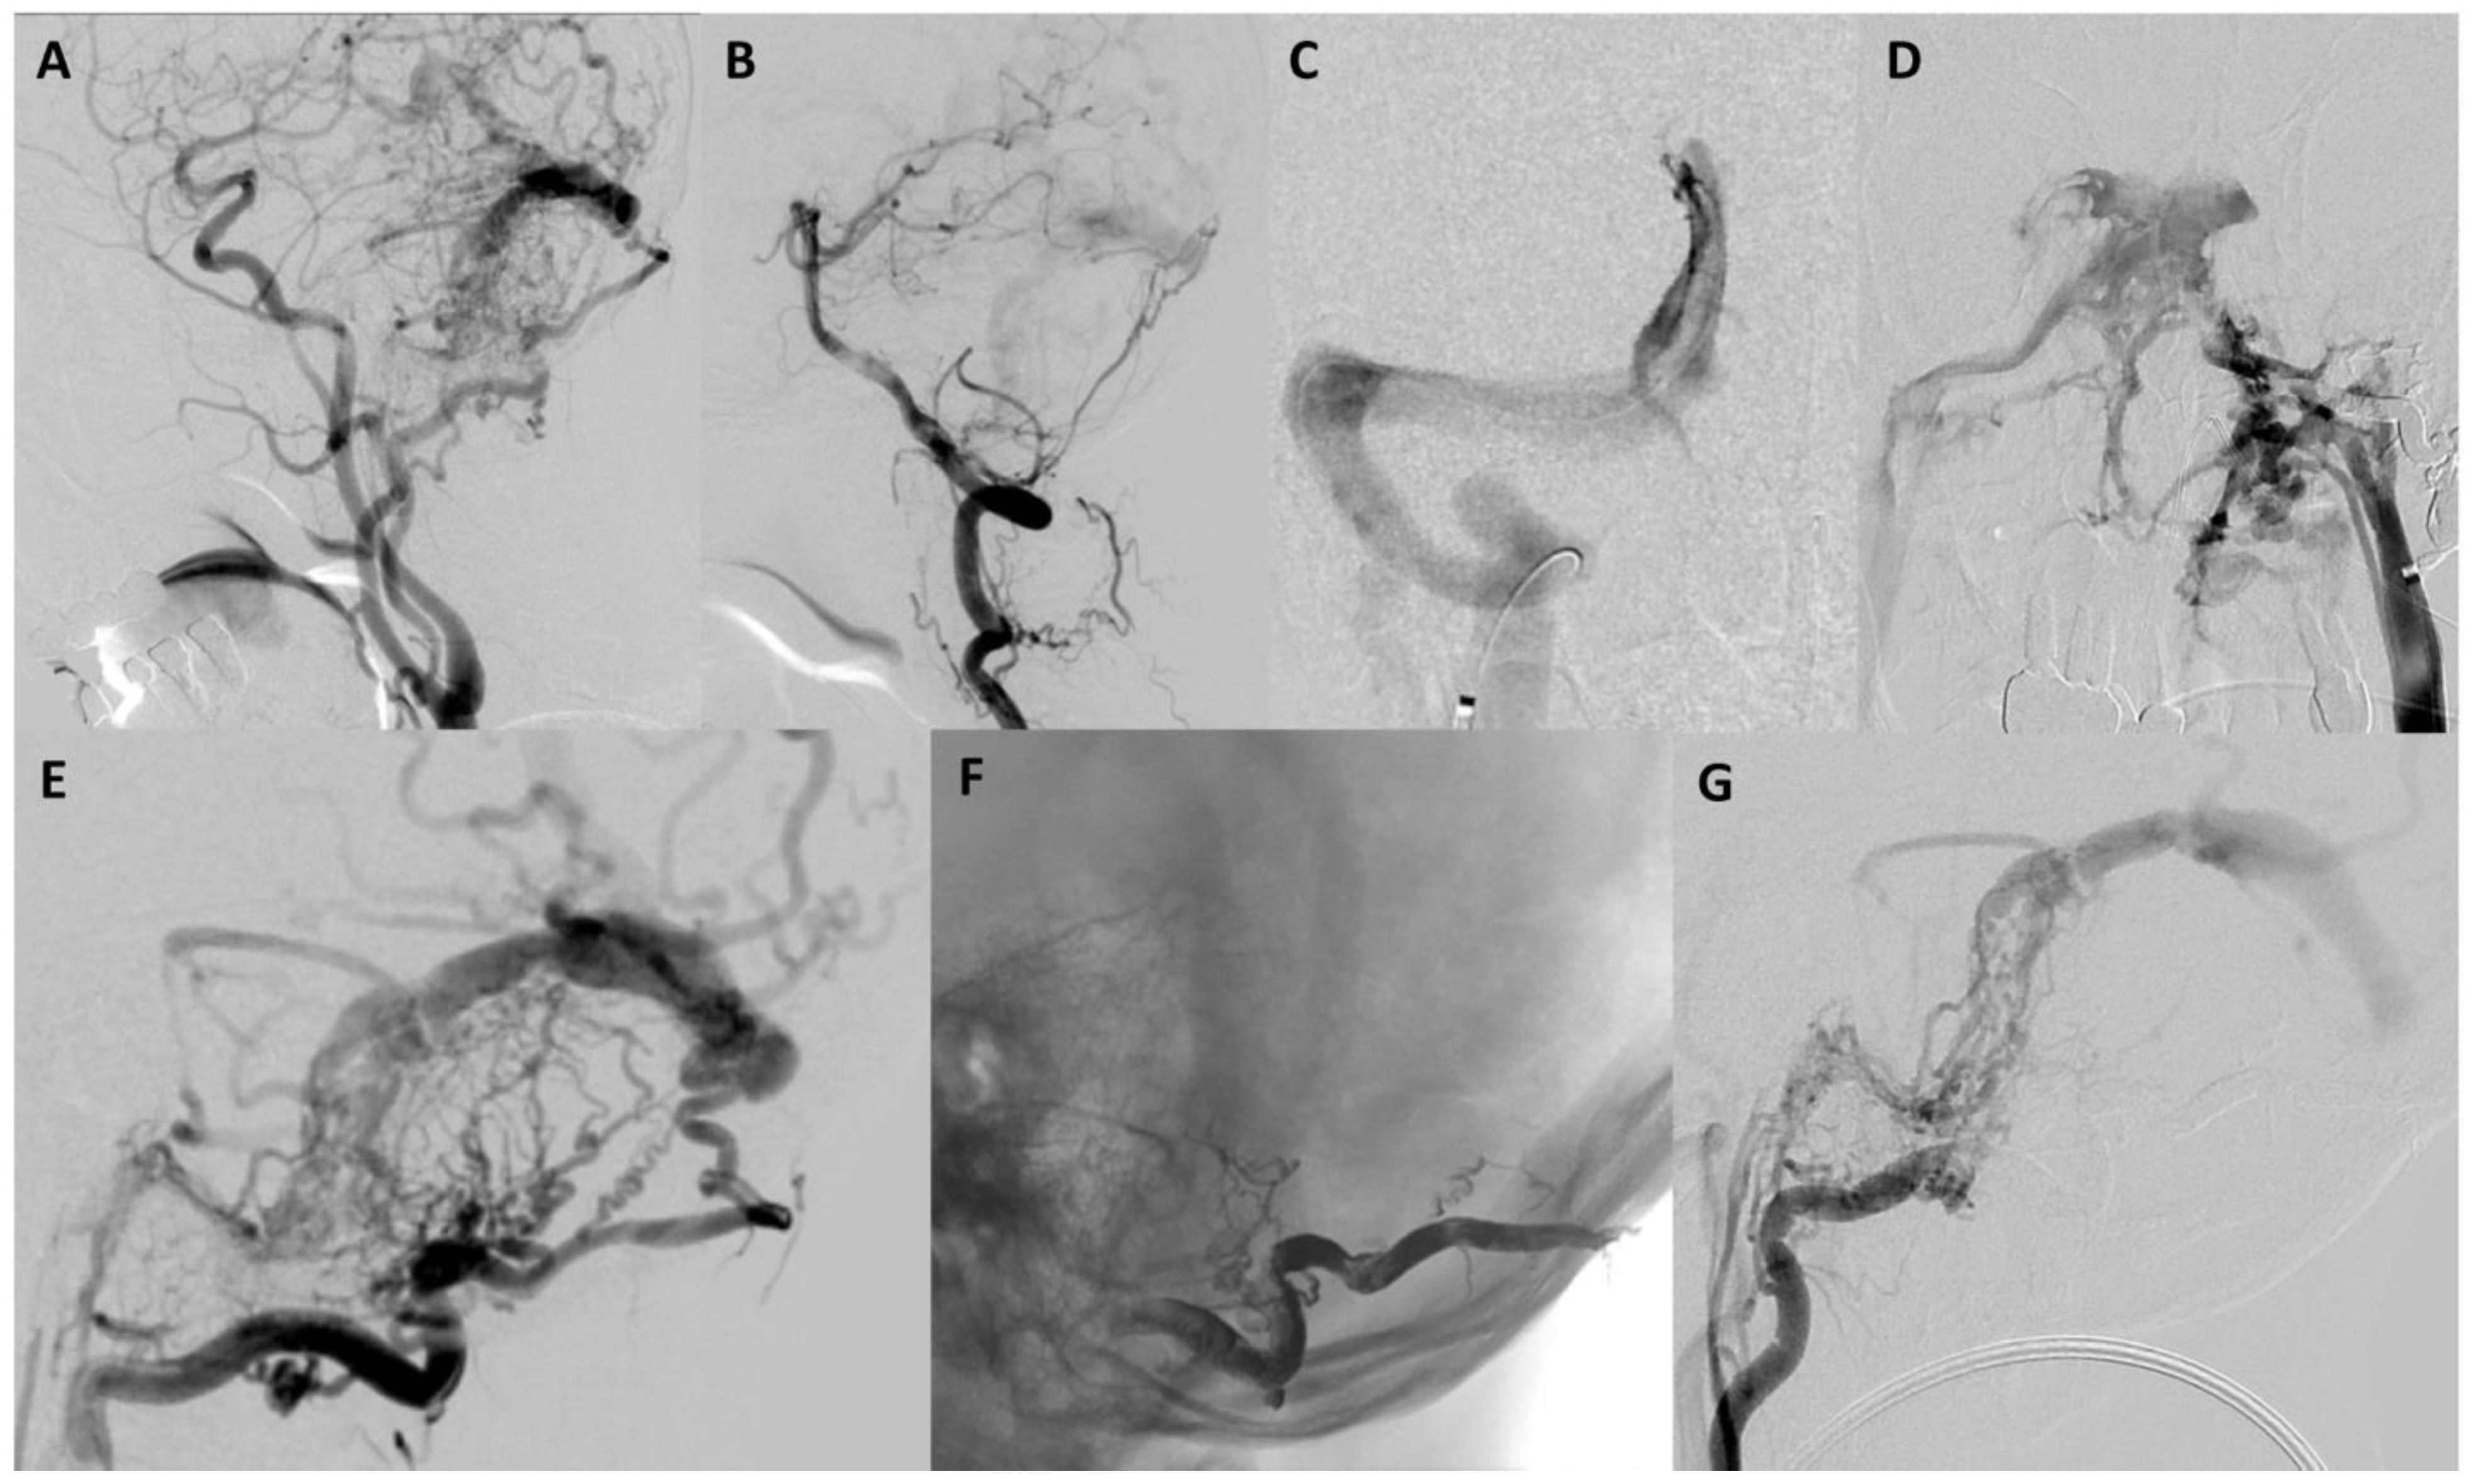

A 72-year-old male presented with the primary complaint of persistent headache for two months. Additionally, he complained of gradually progressing “brain fog” and fatigue over the course of several years. There was also left-sided pulsatile tinnitus that subtly existed over several years but worsened in the preceding two months. CT and CTA head and neck were obtained, which showed possible early filling of the right cavernous sinus, increased vascularity around the left sigmoid–transverse sinus junction, and dilated bilateral cortical veins, more notable on the left (Figure 1). The patient was recommended to undergo cerebral angiography which revealed a Borden II/Cognard IIa+b DAVF (Figure 2).

Given the incomplete occlusion of the DAVF in stage one, the patient was scheduled to undergo a second stage treatment with venous embolization of the fistula four weeks after the initial intervention. At that time, angiography confirmed persistent residual Borden II/Cognard IIa+b DAVF supplied predominantly by additional left occipital artery branches, the left inferolateral trunk, and the left posterior meningeal artery. Numerous dilated and tortuous cortical veins with delayed contrast washout were present, consistent with underlying global venous hypertension. Furthermore, there was no filling of the left transverse sinus during the venous phase, confirming it was not being utilized for normal venous egress and that it was an appropriate target for transvenous embolization. Several attempts were made to access the left transverse sinus. There was no communication across the torcula from the contralateral right transverse sinus (Figure 2C). Furthermore, the left inferior sigmoid sinus was occluded without a connection to the ipsilateral internal jugular vein (Figure 2D). Therefore, transfemoral percutaneous catheterization of the left transverse and sigmoid sinus for embolization was not possible.

The following day, direct access to the left transverse sinus was obtained with neurosurgical burr hole access. In the operating room, the patient was placed in the supine position with his head turned to the right. His hair was shaved, lines were drawn for the incision location, and the patient was covered with sterile draping. Under general anesthesia, an initial incision was made to the bone to gain access to the skull. A high-speed drill was used to create the burr hole over the left transverse sinus. Under Brain Lab neuronavigational guidance, the left transverse sinus was located and a micropuncture needle was used to access the sinus. A microwire was carefully advanced under fluoroscopy through the needle into the target segment of the transverse sinus (Figure 3). Once placed, the needle was removed, and a micropuncture sheath was inserted over the wire. A microcatheter was advanced over a microwire through the micropuncture sheath into the left transverse sinus. Under roadmap guidance, coils were placed with no evidence of residual arteriovenous shunting at the end of the procedure (Figure 3).

Figure 2. (A) Lateral left common carotid angiography showed a left transverse–sigmoid junction dural arteriovenous fistula (Borden II/Cognard IIa+b) supplied by multiple occipital artery branches, the middle meningeal artery, the ascending pharyngeal artery, and the inferolateral trunk. (B) Lateral left vertebral angiography showed there is also supply from the artery of the falx cerebelli. (C) Anteroposterior torcula venography showed there is no communication from the right transverse sinus to the left transverse sinus. (D) Anteroposterior left internal jugular venography showed there is no communication with the left sigmoid sinus consistent with occlusion. (E) Lateral left occipital angiography showed multiple feeders to the left transverse–sigmoid junction dural arteriovenous fistula. (F) The lateral unsubtracted image showed the Onyx cast in the occipital artery after embolization. (G) Lateral left occipital angiography post Onyx embolization showed a reduction in arteriovenous shunting by about 30%.

Figure 3. (A) Head positioning for the burr hole procedure. (B) A small incision was made, and a burr hole was drilled. (C) Direct sinus access was achieved with a micropuncture needle. (D) Catheterization of the left sigmoid sinus. (E) Lateral oblique left sigmoid venography showed good catheter placement in the left sigmoid sinus. (F) The lateral oblique unsubtracted image showed the coil mass after embolization of the left transverse–sigmoid junction. (G) Final lateral oblique left common carotid angiography showed cure of the dural arteriovenous fistula with no residual shunting.